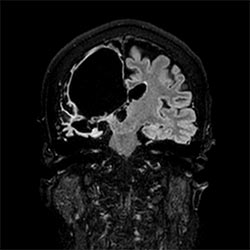

MR görüntülemeyi birçok farklı kontrast tiplerinde ve sekanaslarda yapabilen, 2D ve 3D görüntülemeleri hızlandıran Compressed SENSE hakkında daha detaylı bilgilenmek için Kantonsspital Winterthur'ın (İsviçre) deneyimlerinden faydalanın.